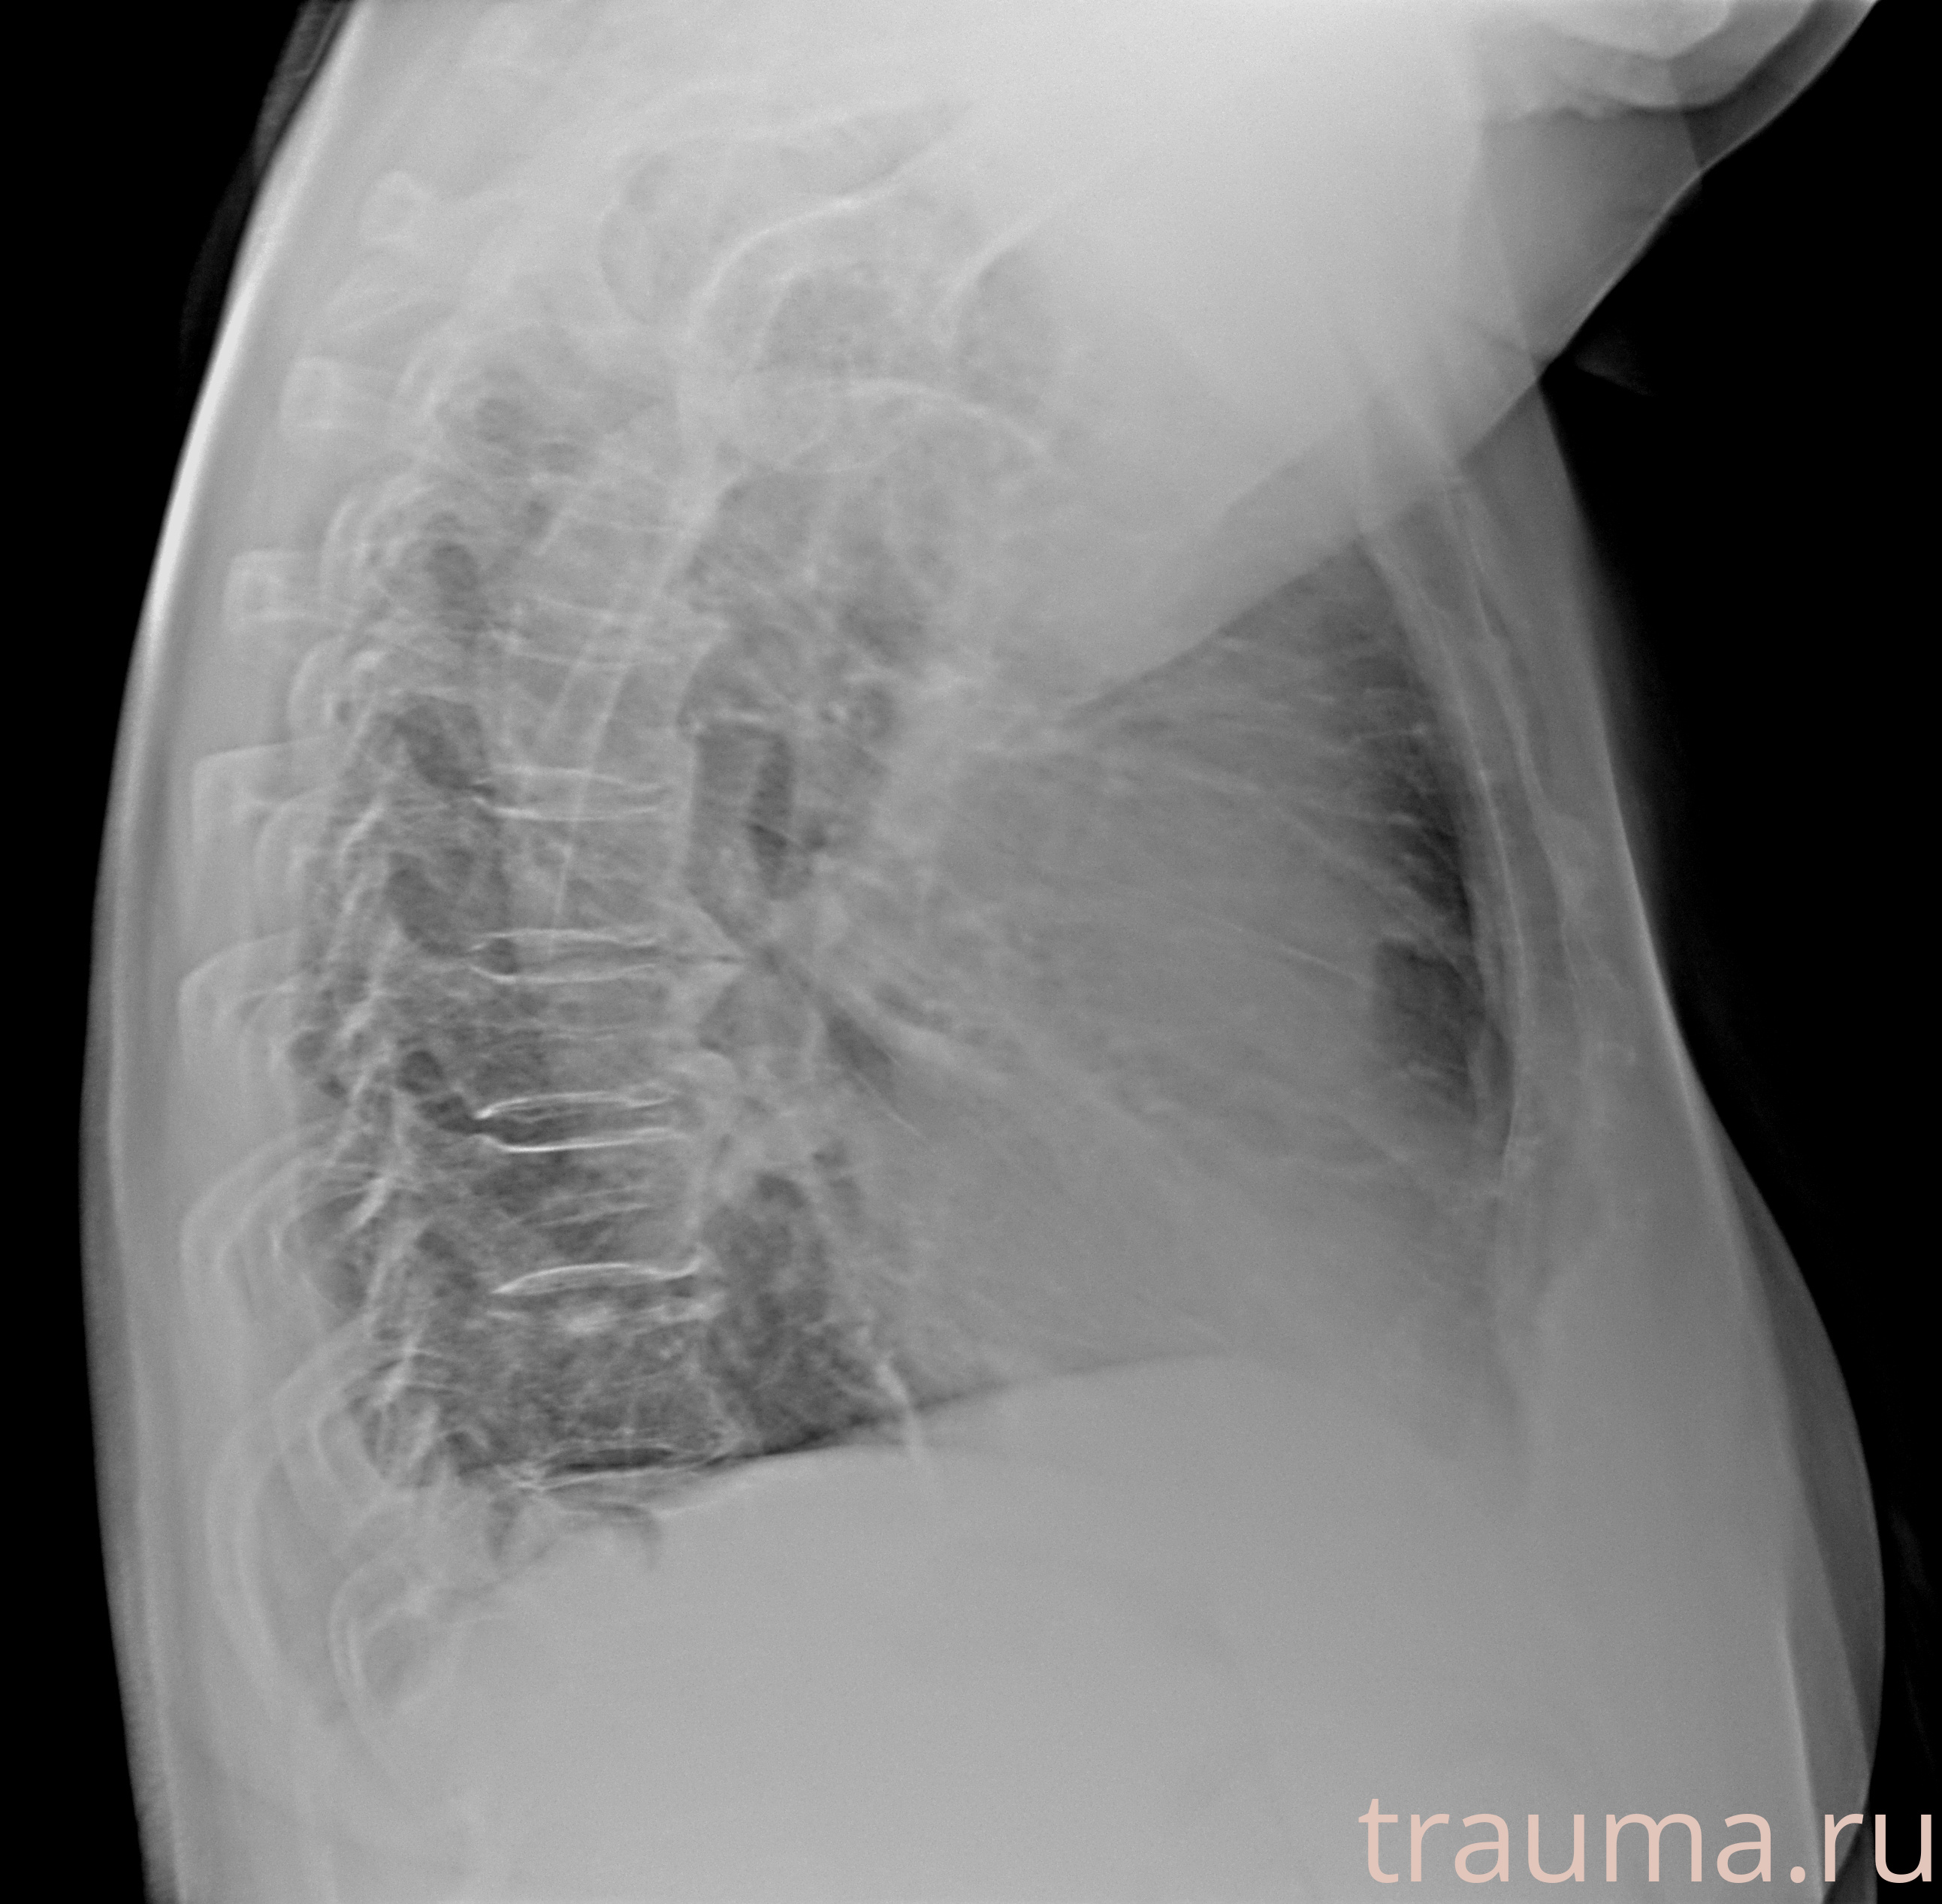

Рентгенограммы

Рентген на дому: по вашему адресу приезжает врач-рентгенолог, травматолог-ортопед с мобильным рентгеновским аппаратом, проводит диагностику травмы или заболевания, делает необходимые рентгенограммы, дает рекомендации по дальнейшему лечению. Получить качественные снимки в домашних условиях возможно благодаря уникальной методике, разработанной МосРентген Центром для института  Склифосовского